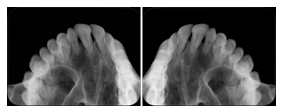

2 Occlusal Vertical Maxilla A Dental Image Layout

DL-C001A

Reference: DL-C001-U1L0

Reference: DL-C001-U2L0

00

Occlusal

18, 17, 16, 15, 14, 13, 12, 11, 13, 12, 11

01

21, 22, 23, 24, 25, 26,27, 28

2 Occlusal Vertical Mandible A Dental Image Layout

DL-C002A

Reference: DL-C002-U0L1

Reference: DL-C002A-U0L2

10

48, 48, 47, 46, 45, 44, 43, 42, 41

11

31, 32, 33, 34, 35, 36, 37, 38

2 Occlusal Horizontal Maxilla A Dental Image Layout

DL-C003A

Reference: DL-C003-U1L0

Reference: DL-C003-U2L0

18, 17, 16, 15, 14, 13, 12, 11, 13, 12, 11, 21, 22, 23, 24, 25, 26,27, 28

2 Occlusal Horizontal Mandible A Dental Image Layout

DL-C004A

Reference: DL-C004-U0L1

Reference: DL-C004-U0L2

48, 48, 47, 46, 45, 44, 43, 42, 41, 31, 32, 33, 34, 35, 36, 37, 38